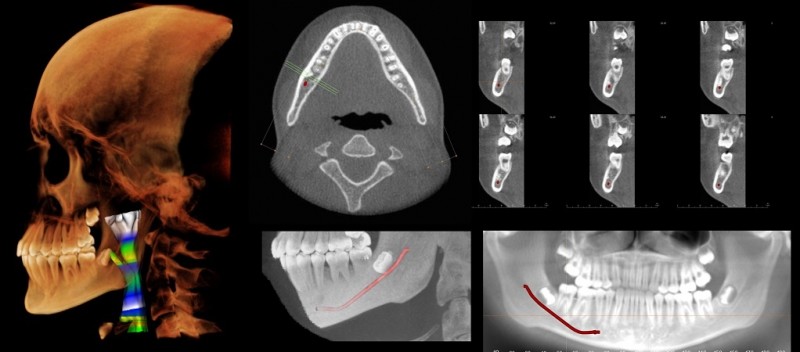

Projects like this are just part of a shift toward "digital dentistry," as technology transforms a profession that was once mostly dependent on manual skills. With the aid of computers, dentists can now produce crowns in their office in about the time it takes to make a pair of eyeglasses, for example. They can also use software to design drill guides customized for their patients' jaws, to help place implants more accurately.

Imaging technologies such as MRIs and cone-beam CT scans, which produce a 3-D cross-sectional image, have expanded the ways dentists can explore beyond the teeth and gums. Panoramic X-rays, which capture the whole mouth in one two-dimensional image, are commonly used during checkups and to plan dentures, implants, braces, and extractions.